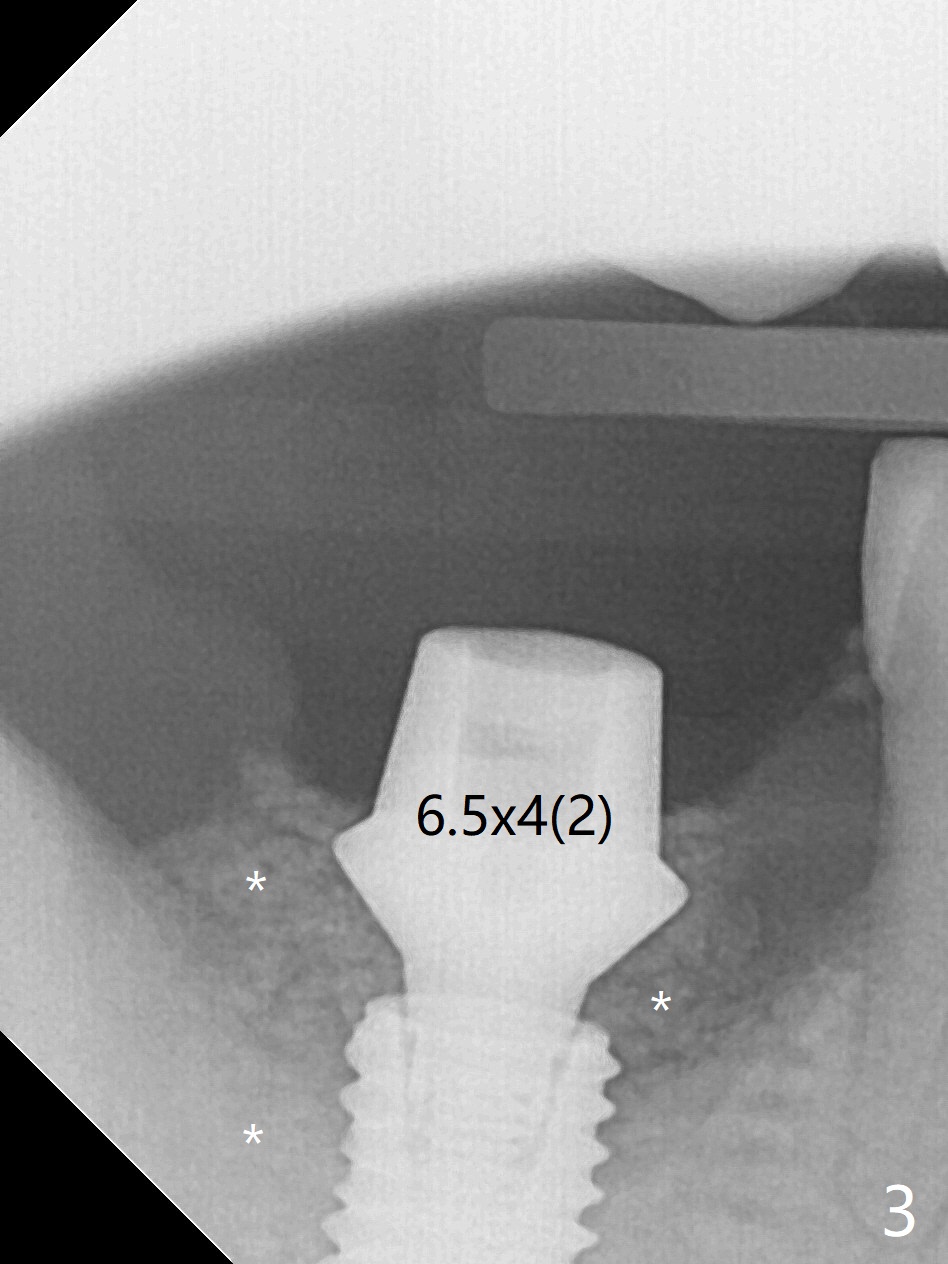

The morning case shows that to avoid Inferior Alveolar Neuropathy associated with 2nd molar implant placement, three measures should be adopted, no block anesthesia, no pressure on the distal end of the distal end guide and no over deep placement. In fact pain control is difficult with severe chronic periodontitis at #31. After repeated infiltration injection, the most effective step of anesthesia is slow speed of osteotomy with gentle pressure. The 1st intraop PA is taken when the depth is reached with a 2.2 mm pilot drill (Fig.1 (yellow dashed line: superior border of the Inferior Alveolar Canal)). The 2nd purpose of the PA is to make sure that the osteotomy is establish in the mesial slope of the socket (red dashed line). As drills increase in diameter, the patient experiences pain. Since the bone density is high, it is hard to place 5x10 mm implant to the lowest space (Fig.2 *, ~ 60 Ncm). For compensation, bone graft (Fig.3 *) is packed securely around the implant before and after abutment insertion. After fabrication of an immediate provisional, periodontal dressing is applied around the provisional and socket to prevent graft leakage. Smoke cessation/reduction is encouraged. In fact the patient returns 11 months postop (the 1st time postop), partly due to coronavirus. The immediate provisional is lost, but the distal defect has apparently been repaired (Fig.4*). A 4 mm cuff abutment is changed to due to enough occlusal clearance. The abutment is completely seated. Oral hygiene is poor with 1/2 ppd of smoke. SRP was done in the lower right quadrant when the implant was placed. When the crown is delivered 1 year postop, the patient mentions #18 mobility. SRP is done in the lower left quadrant. The bone is stable 10 months post cementation (Fig.5).